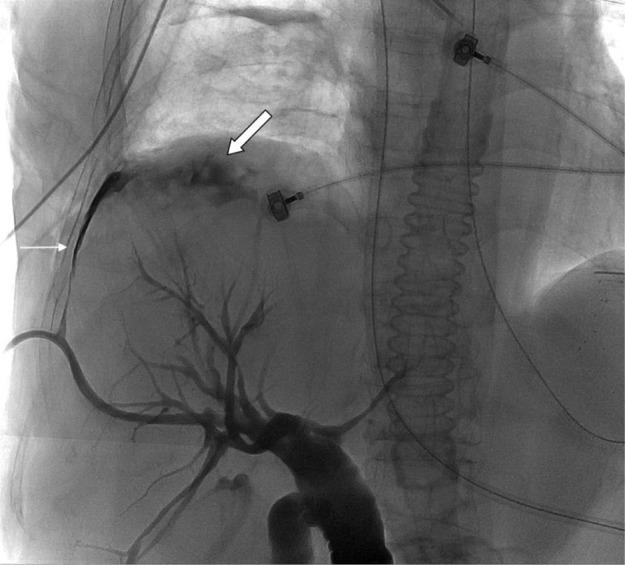

Biliopleural fistula (BF) and formation of biliopleural effusion is a rare complication following percutaneous transhepatic biliary drainage (PTBD). It occurs when the pleura is traversed by the catheter before entering the bile duct. Biliopleural fistula should be suspected when right side pleural effusion develops following the PTBD procedure. The diagnosis of biliopleural fistula is made when greenish pleural fluid with high concentration of bilirubin is aspirated. Here we present a case where a patient develops a biliopleural fistula following PTBD due to obstructive jaundice caused by neuroendocrine tumor of pancreas. Biliopleural fistula was disclosed after a scheduled catheter replacement procedure. Treatments of biliopleural fistula include thoracentesis with drainage tube installation into pleural space. In addition, a drainage tube was installed through percutaneous transhepatic gallbladder drainage (PTGBD) to reduce the bile induced pressure. Surgical repair of fistula was performed after the conservative treatment was unsuccessful. The patient expired 5 days after surgery due to respiratory failure.